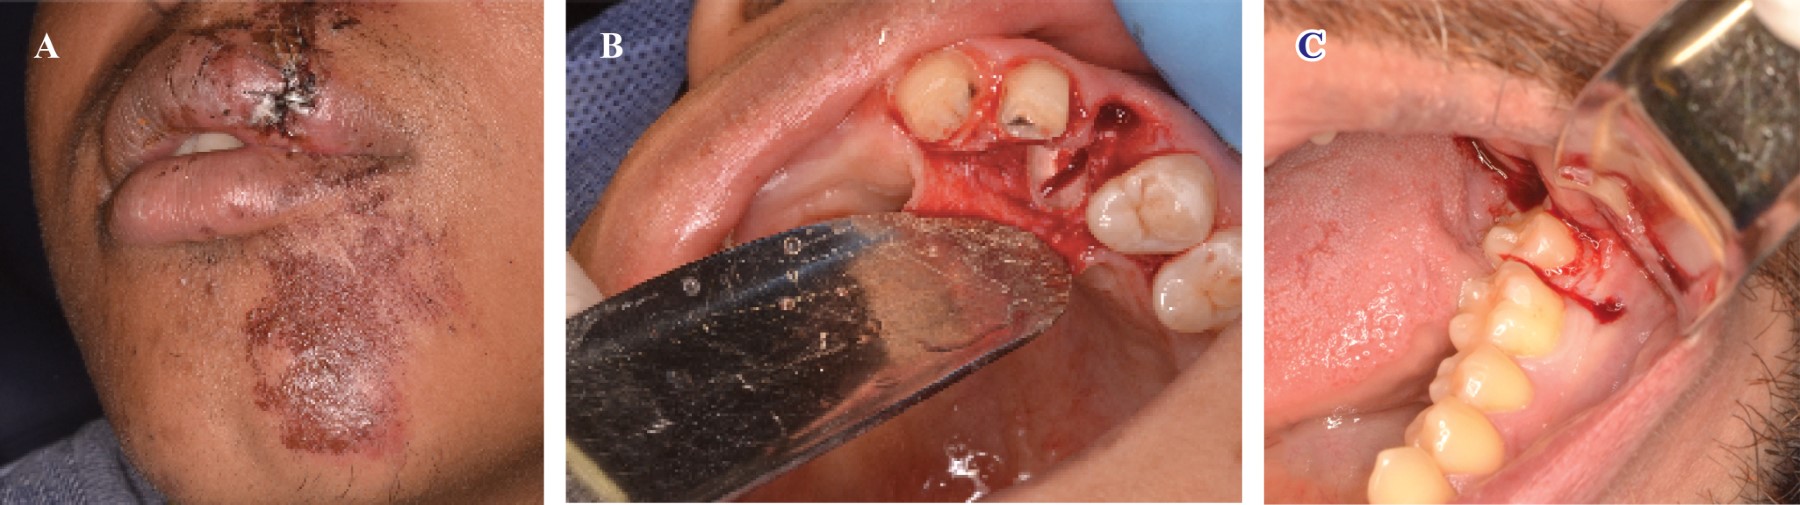

Figure 1

Figure 2

Figure 3